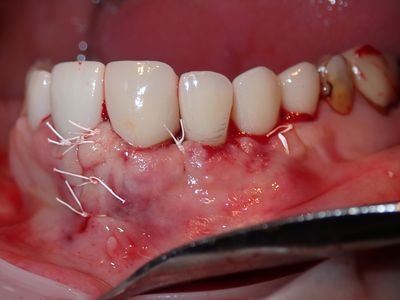

implant was placed and loaded. Pt has pain to tapping implant crown, no other symptoms, esthetics are acceptable. Scan shows implant out of bone buccal. discussion on flap design, started with a small flap but with amount of bone loss, access was key, dropped a vertical. thorough cleaning around implant. grafted site with sticky bone from equal amounts mineralized cortical allograft, xenograft and synthetic bone. Collagen membrane soaked in prf fluid placed defect with 4 membrane tacks. fibrin membrane used overtop. Will assess symptoms in 5 months